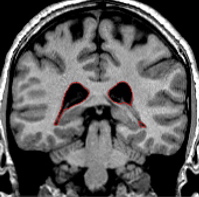

| Part II - Medial portion of the ILV Moving posteriorly, when the amygdala is gone or almost gone, it may be difficult to determine the medial extent of the inferior lateral ventricle. Depending on the brain, it may appear as the inferior lateral ventricle is continuous with the exterior outline. There is in actuality a small membrane called the tele choroides of the lateral ventricle that separates the inferior lateral ventricle from the outside of the brain. Brightening the screen may help to see this thin membrane. If it is not possible to see this border, discretion must be used. The inferior lateral ventricle extends medially to the subiculum, and not past. Once you have made a decision as to the most medial extend of the inferior lateral ventricle, remain consistent with this decision through the posterior course of the brain. As you continue to move more posterior, this will no longer be an issue. |

| Part III - Posterior portion of the ILV Toward its posterior endpoint, the ventricle will appear as a small circle which is adjacent to the ventral-lateral corner of the hippocampus. The course of the inferior lateral ventricle is sometimes interrupted, and may be absent for a slice or two but then reappear. Use of the projection lines will verify the extent of the ventricle at its anterior and posterior limits. At its posterior endpoint, the inferior lateral ventricle will become continuos with the lateral ventricle outline. |